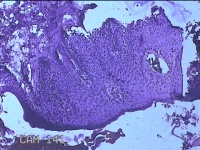

后颈部结节

性别

女

年龄

25岁

临床诊断

皮下结节

一般病史

发现后颈部“黑痣”20余年,伴近日局部瘙痒不适。

标本名称

大体所见

灰白粉红色带皮肤结节0.8x0.7x0.3cm一个,表面糜烂,切开结节呈实性,切面灰白粉红色,质软。

图1

皮内痣